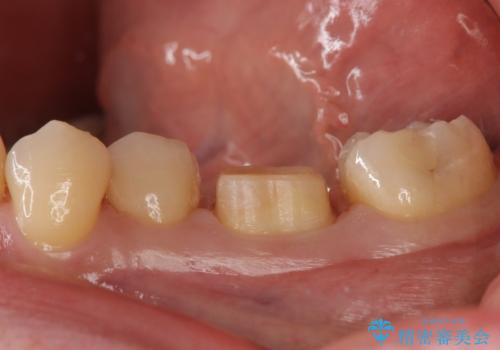

- 左下に詰めた樹脂の変色を主訴に来院されました。

同じ樹脂の材料で詰め直しをしたところでまた変色してしまうリスクが高いため、セラミックでの治療となりました。